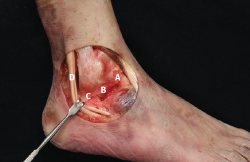

Figura 2. Anatomía del complejo lateral del tobillo. A: fascículo superior del ligamento talofibular anterior (LTFA); B: fascículo inferior del LTFA; C: ligamento calcaneofibular (LCF); D: tendones peroneos.

- Inicialmente, con los ligamentos íntegros (Figura 2), realizamos las maniobras anteriormente mencionadas (CA, EV) y registramos la movilidad angular detectada por el sensor en los 3 planos espaciales.